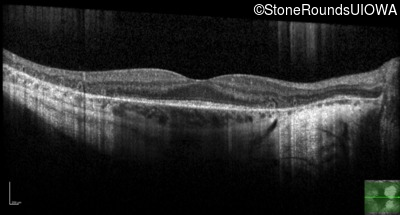

Age at visit: 30 years